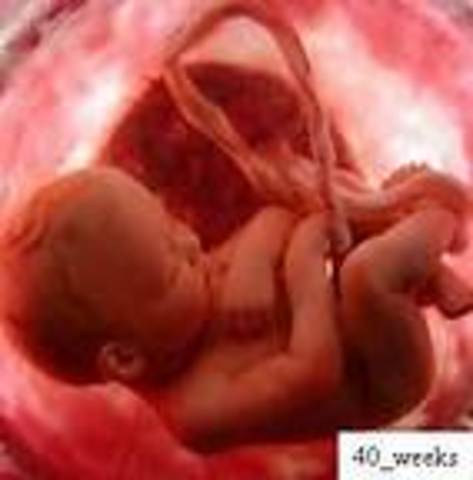

• Week 40

Week 40

.•You have now reached the time of delivery.

•All systems are developed and ready to go.

•Now it is just a matter of time.

•Baby is about 20 inches (51cm) and weighs approximately 7.5 pounds (3.5 kg).

•The head has a diameter of about 4 inches (10 cm).

•The contractions could begin at any moment.